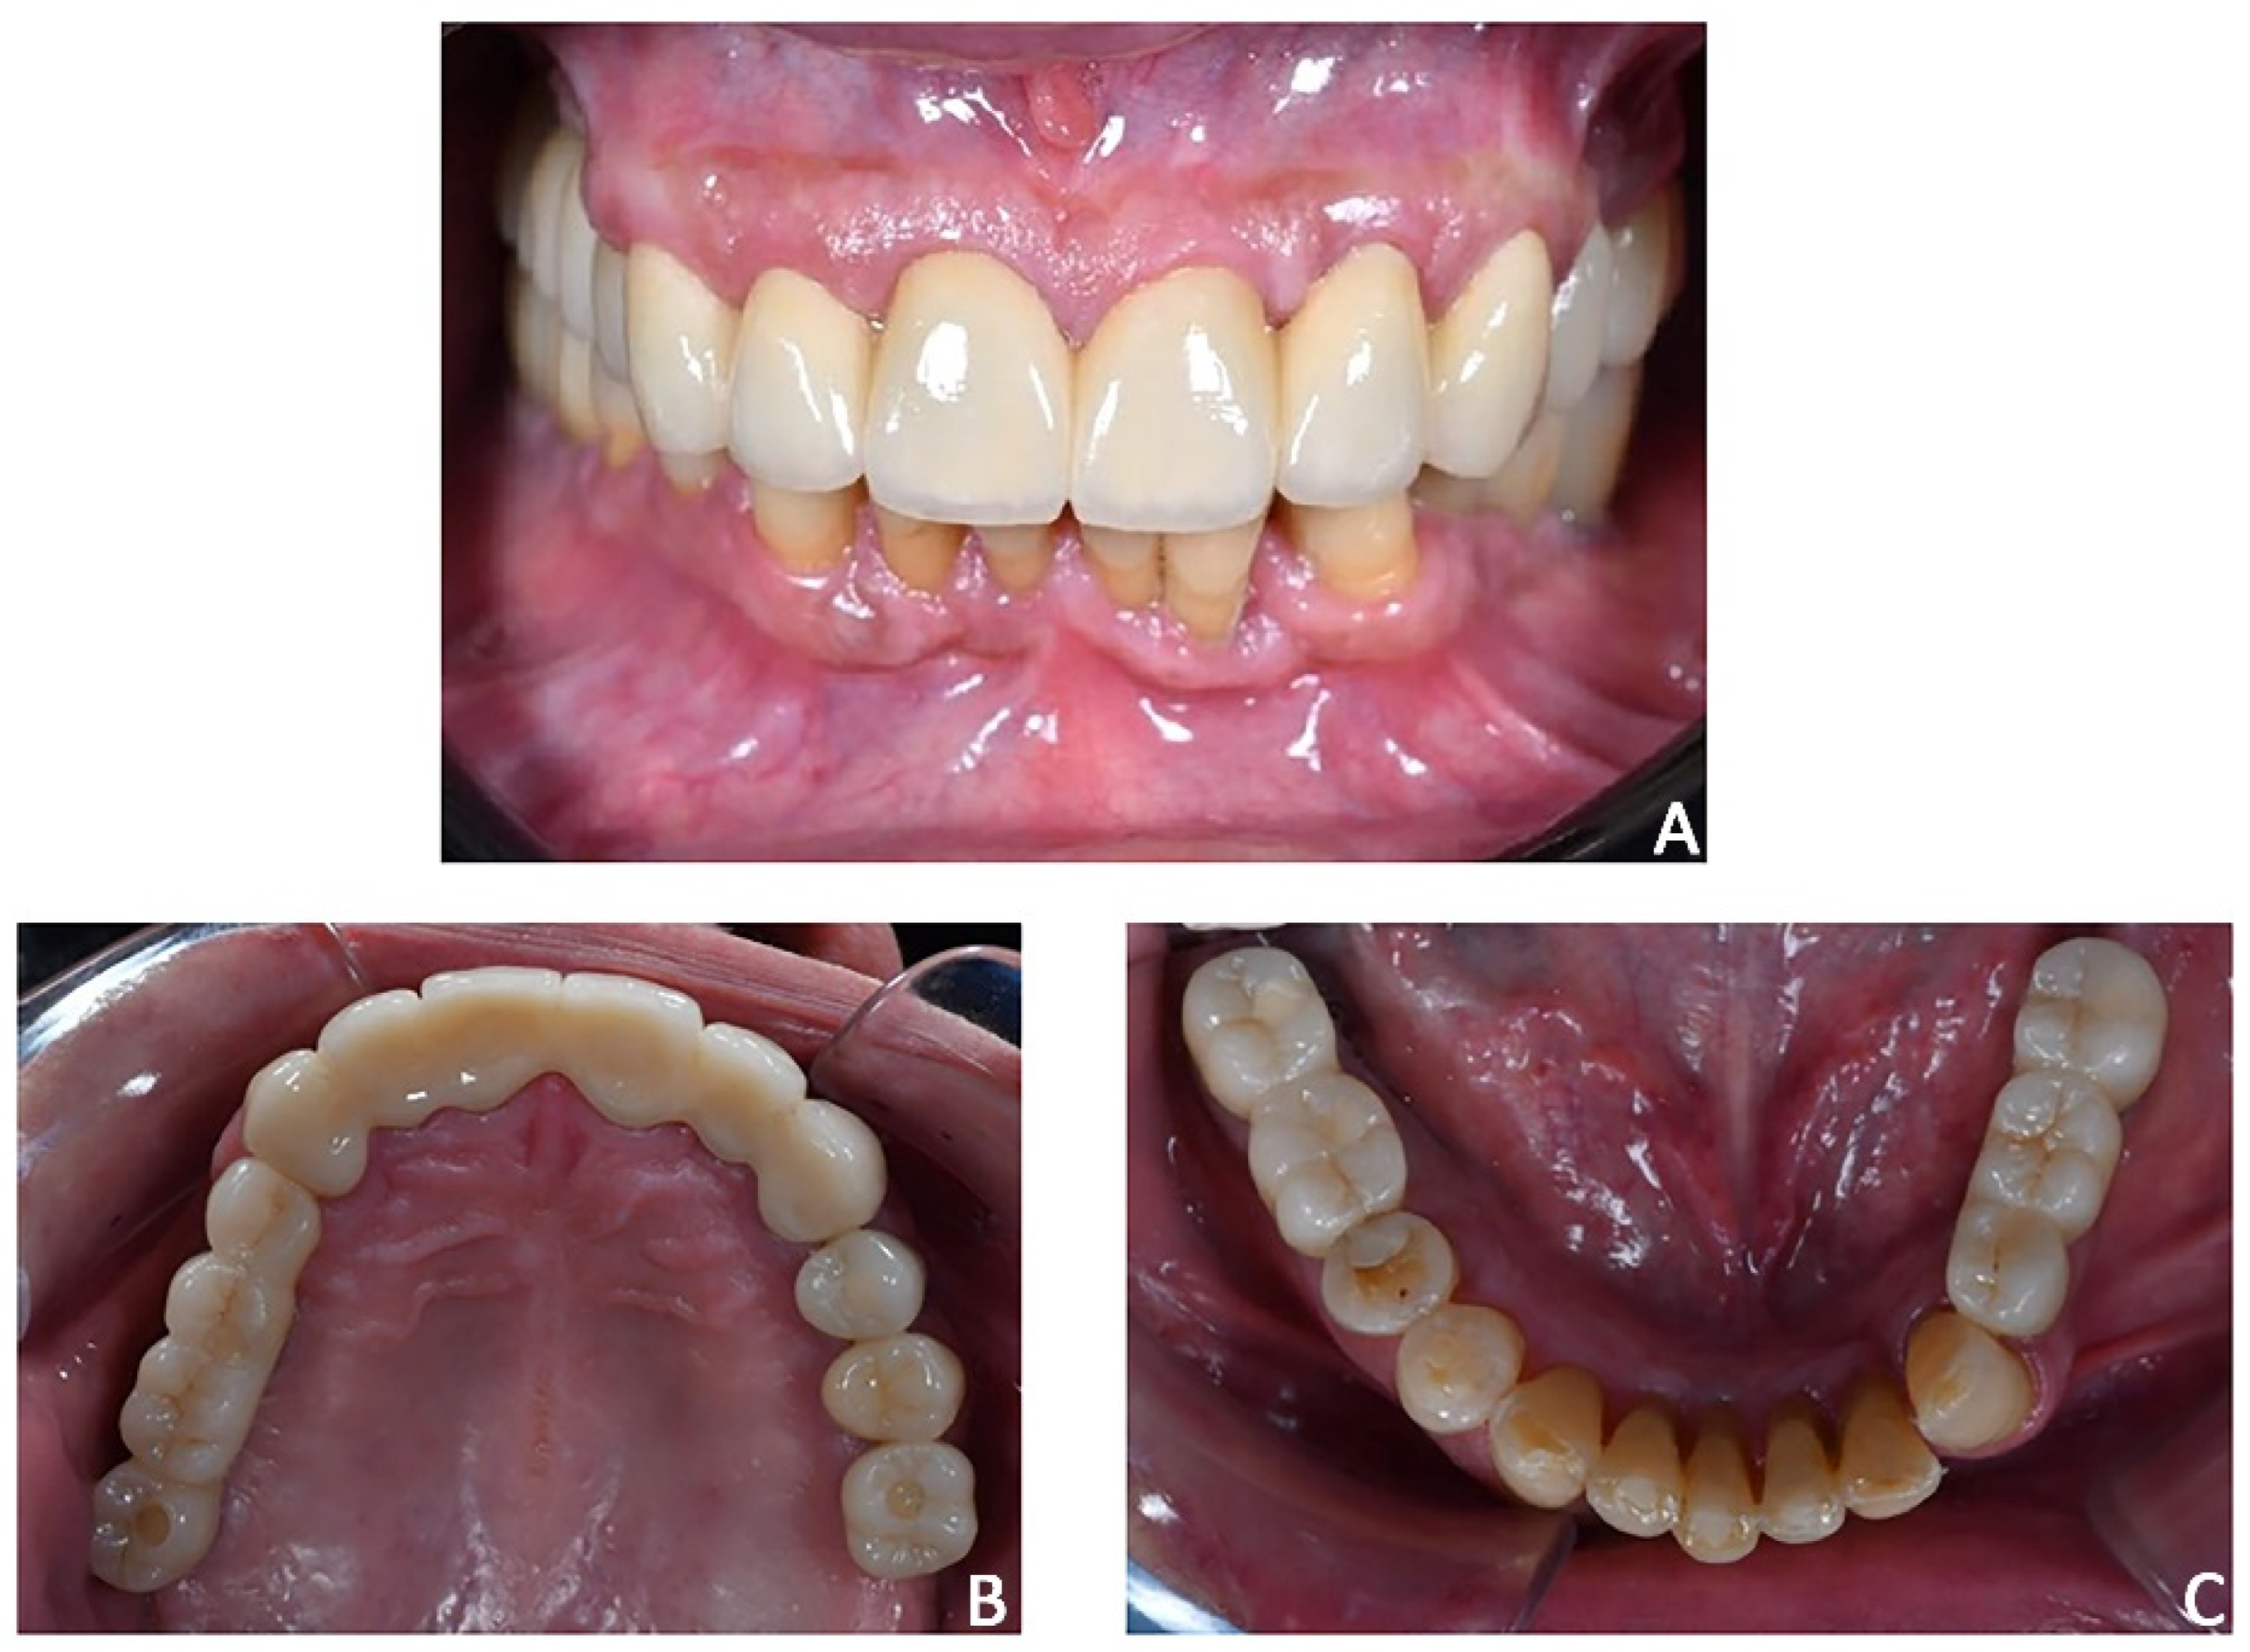

Figure 21. Case 3. Post-treatment smile aesthetics. (A) frontal smile view; (B) 3/4 right smile view; (C) 3/4 left smile view.

The planning of the prosthetic rehabilitation, including the augmentation of vertical dimension and the orthodontic treatment, allowed for the achievement of an extremely satisfactory and predictable result from aesthetic and functional perspectives (Figure 21).